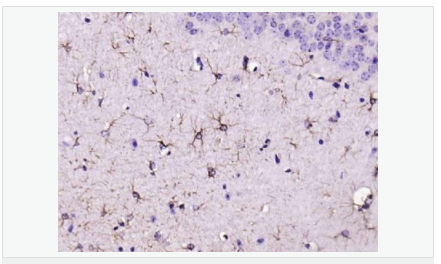

| 產(chǎn)品應用 | WB=1:500-2000 ELISA=1:5000-10000 IHC-P=1:200-1000 IHC-F=1:200-1000 Flow-Cyt=1μg/Test ICC=1:100 IF=1:200-800 (石蠟切片需做抗原修復) not yet tested in other applications. optimal dilutions/concentrations should be determined by the end user. |

| 產(chǎn)品介紹 | This gene encodes one of the major intermediate filament proteins of mature astrocytes. It is used as a marker to distinguish astrocytes from other glial cells during development. Mutations in this gene cause Alexander disease, a rare disorder of astrocytes in the central nervous system. Alternative splicing results in multiple transcript variants encoding distinct isoforms. [provided by RefSeq, Oct 2008] Function: GFAP, a class-III intermediate filament, is a cell-specific marker that, during the development of the central nervous system, distinguishes astrocytes from other glial cells. Subunit: Interacts with SYNM. Isoform 3 interacts with PSEN1 (via N-terminus). Subcellular Location: Cytoplasm. Note=Associated with intermediate filaments. Tissue Specificity: Expressed in cells lacking fibronectin. Post-translational modifications: Phosphorylated by PKN1. DISEASE: Defects in GFAP are a cause of Alexander disease (ALEXD) [MIM:203450]. Alexander disease is a rare disorder of the central nervous system. It is a progressive leukoencephalopathy whose hallmark is the widespread accumulation of Rosenthal fibers which are cytoplasmic inclusions in astrocytes. The most common form affects infants and young children, and is characterized by progressive failure of central myelination, usually leading to death usually within the first decade. Infants with Alexander disease develop a leukoencephalopathy with macrocephaly, seizures, and psychomotor retardation. Patients with juvenile or adult forms typically experience ataxia, bulbar signs and spasticity, and a more slowly progressive course. Similarity: Belongs to the intermediate filament family. SWISS: P14136 Gene ID: 2670 Database links: Entrez Gene: 2670 Human Entrez Gene: 14580 Mouse Omim: 137780 Human SwissProt: P14136 Human SwissProt: P03995 Mouse Important Note: This product as supplied is intended for research use only, not for use in human, therapeutic or diagnostic applications. 星形膠質細胞標志物 (Astrocyte Marker) GFAP是一個56kDa的中間絲蛋白(intermediate filament,IF),在中樞神經(jīng)系統(tǒng)發(fā)育期是一個特異性的標志物,以區(qū)別星形細胞和其它膠質細胞。GFAP表達在皮層和海馬,急、慢性皮質酮治療時表達減少。 GFAP可以和人、大鼠、小鼠的GFAP反應,在正常和腫瘤性的星形膠質細胞陽性表達,而神經(jīng)節(jié)細胞、神經(jīng)元、成纖維細胞、少突膠質細胞和這些細胞來源的腫瘤細胞陰性表達,主要用于星形膠質瘤等中樞神經(jīng)系統(tǒng)腫瘤的診斷和鑒別診斷,GFAP的缺乏可導致AD病。 |